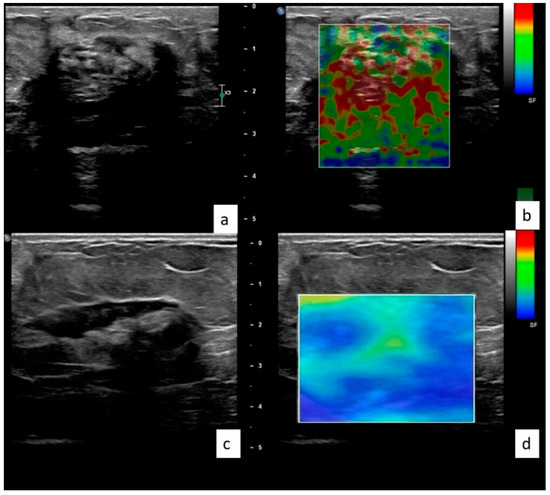

Figure 2. 38 year old female with pathologically confirmed granulomatous mastitis. The lesion was located on the right breast, upper quadrant. The patient was treated locally. Elastographic examinations at the time of diagnosis (a,b) and 8 weeks after treatment (c,d) reveal that the lesion’s elasticity value (kPa) decreased by 57.9%, from 77.5 to 32.6 kPa.